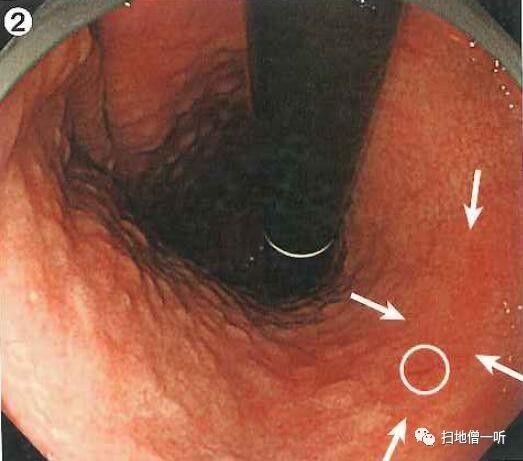

A:第二个病变胃癌在图1及图2。(此次检查被漏诊)

回顾性观察图1可见胃窦部后壁小片状发红粘膜,胃窦蠕动时观察不佳。图2可见凹陷型病变,鉴于没有通过抽气吸气等详细观察,故此次漏诊。

教训:胃蠕动较快时等蠕动过去后再详细观察,必要时喷洒染色剂有助于防止漏诊。

半年后再次行内镜检查所见:胃窦后壁凹陷性病变明显,周围伴反应性隆起。

喷洒靛胭脂后凹陷面更加明显,活检钳帮助下观察病变正面观,病变红色凹陷,边界呈蚕食状,故考虑分化癌诊断。

最终病理诊断:

胃窦后壁,O-IIc,6mm,tub1,T1a (M),UL(-)